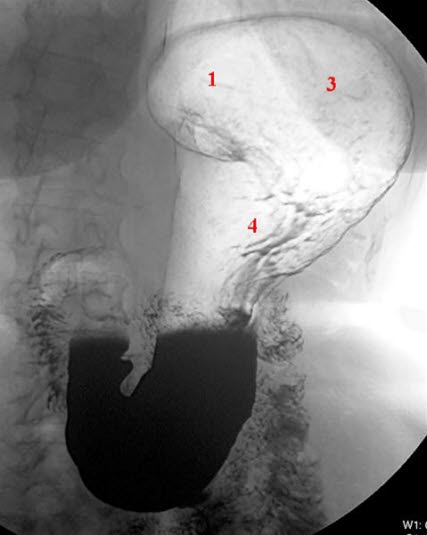

Fra spiserøret kommer maten over i magesekken (ventrikkelen) (se figur). En fylt magesekk rommer vanligvis ca. 1,5 liter. Den ligger øverst i midtre del av bukhulen og har en avlang og krummet fasong. Magesekken har en kort og en lang side, og den smalner av før den går over i tolvfingertarmen (duodenum). Saltsyre og stoffer som starter nedbrytingen av føden (eks. pepsin), lages i slimhinnen i magesekken. Slimhinnen er kledd med et beskyttende slimlag som hindrer saltsyren i å etse hull på magesekken. Den nedsvelgde maten eltes ved at magesekken trekker seg sammen og utvider seg (såkalt peristaltisk aktivitet). Tolvfingertarmen har en C-form og er ca. 25 cm lang. Gallegangen og utførselsgangen til bukspyttkjertelen tømmer seg i tolvfingertarmen. Både galle og bukspytt er nødvendig for nedbrytningen av føden i tarmen.

Et magesår oppstår enten i magesekken eller i tolvfingertarmen (se figur). Sår i tolvfingertarmen forekommer ca. 5 ganger så hyppig som sår i magesekken.

Undersøkelsen fremstiller form, posisjon, slimhinnefolder, sammentrekninger og bevegelser av magesekken og øvre del av fordøyelseskanalen (se røntgenbildene over). Undersøkelsen omfatter vanligvis både øsofagus (spiserør = Ø), ventrikkel (V), duodenum (D) og øvre del av tynntarmen. På fagspråket brukes ofte betegnelsen røntgen Ø+V+D. Undersøkelsen foregår med bruk av kontrast og som regel med såkalt dobbelkontrast-metode, det vil si både kontrastvæske og luft. Røntgen av øvre del av magetarm-kanalen gjøres sjeldnere i dag enn før. Gastroskopi er en mer presis undersøkelse og gir anledning til direkte prøvetaking til mikrobiologiske undersøkelser og mikroskopi av vevsprøver (histologi).

Røntgenlegen ser etter uregelmessige relieff eller konturer i magesekkens vegg. Tiden det tar å tømme magesekken for kontrast, er også en viktig observasjon. Forsinket tømning kan være uttrykk for sykdom. Blant de hyppigste sykdommer som kan påvises, er magesår enten i magesekken eller tolvfingertarmen. Ofte kan det finnes arrforandringer i tolvfingertarmen etter tidligere magesår. Polypper og kreft i magesekken kan påvises med røntgen. Videre utredning gjøres som regel med gastroskopi, ultralyd, CT eller MR.